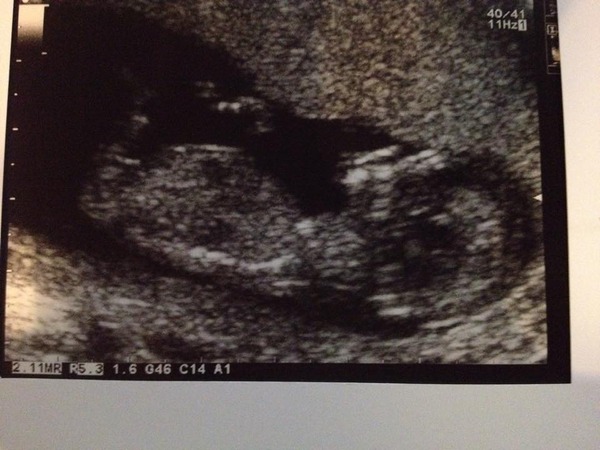

So we had the scan today! I refused to look at the screen till the lady promised me there was a heart beat might have had a small melt down before going in after I remembered my 36 week scan with miniLuna, mrLuna all but had to march me in everything is fine, we have just the one and I've been put forward to 12+5 with a due date of 11th April.

All sounds positive *littleluna89+, lovely pic!

I had my scan this afternoon, it was having a good old stretch, lol! All looked good so far, I'm very relieved. The sonographer was lovely. She said she thought she might have seen something to suggest boy but it's far too early to tell really so don't buy anything!!! Lol! Will be fun to see if she is right! And I gained 3 days... 12+3, due 14th April Smile